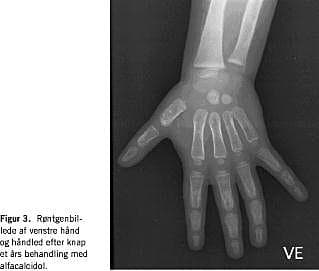

Objektivt fremtrådte barnet psykisk alderssvarende, men den grov- og finmotoriske udvikling var forsinket. Der bemærkedes åbentstående forreste fontanelle, rosenkrans og epifysesvulst ved håndled og knæ. Blodprøverne viste S-calcium-ion 0,83 mmol/l (1,22-1,37) og total S-calcium 1,61 mmol/l (2,17-2,66), S-fosfat 1,12 mmol/l (1,36-2,55) og S-basisk fosfatase 8882 U/l (250-1.000). Der suppleredes med S-parathyroideahormon (PTH) på 86,3 pmol/l (1,1-6,9) og P-25-hydroxy-D-vitamin 84 nmol/l (45-150). Ved en røntgenundersøgelse afsløredes udtalte rakitisforandringer med halisterese og breddeøgede metafyser i hånd- og knæled (Figur 1).